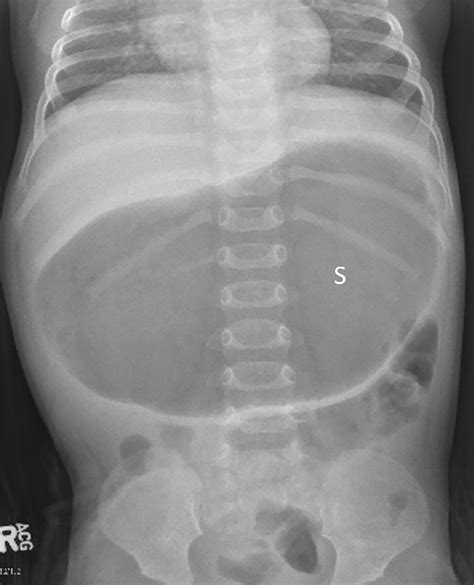

• Bloated Stomach: The baby's stomach may appear bloated or hard to the touch.

• The baby has a distended abdomen that is tender to the touch.

These symptoms may indicate a more serious condition, such as an intestinal obstruction or infection, and require immediate medical attention.

While gas is generally harmless, it can sometimes be a symptom of an underlying medical condition. Some medical conditions that can cause gas in newborns include:

• Intestinal obstruction